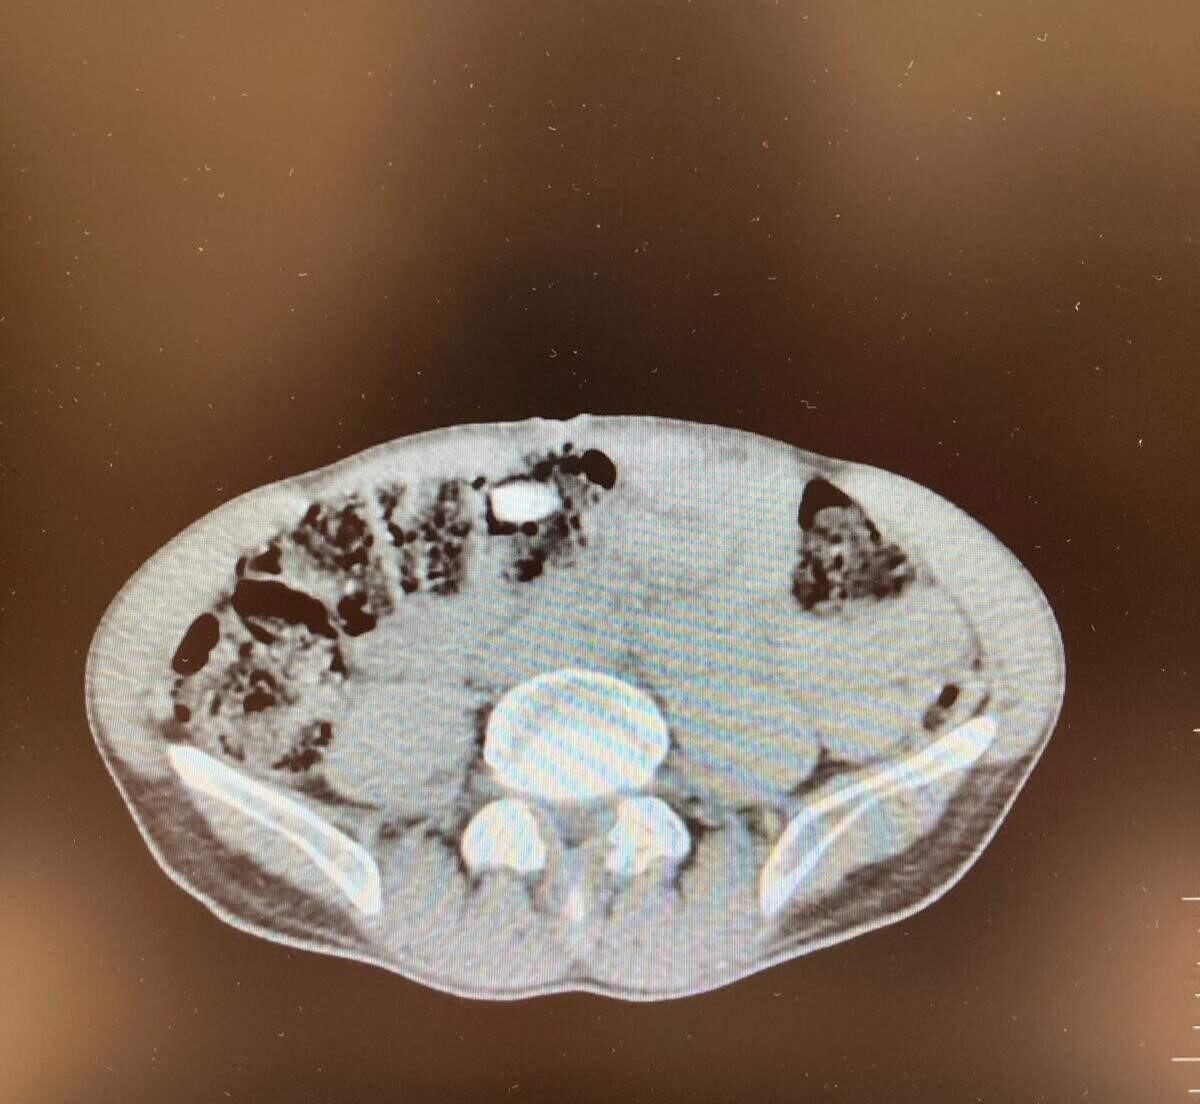

Denizli İl Emniyet Müdürlüğü Narkotik Suçlarla Mücadele Şube Müdürlüğünce uluslararası uyuşturucu madde ticaretinin önlenmesine yönelik çalışmalar devam ediyor. Yapılan incemeler ve değerlendirmeler sonucunda Denizli’ye havayoluyla yolculuk eden yabancı uyruklu şahsın uyuşturucu madde getireceği tespit edildi. Şüpheli, Narkotik Suçlarla Mücadele Şube Müdürlüğü ve Çardak Havalimanı Gümrük Muhafaza Bölge Amirliği görevlilerince müşterek yapılan çalışmalar neticesinde yakalandı. Şüphelinin eşyalarında yapılan aramalarda 6 parça halinde giysilere emdirilmiş şekilde 1 kilo 257 gram metamfetamin maddesi ele geçirildi. Yapılan iç beden muayenesinde ise 3 parça halinde 15 adet ecza hap ele geçirildi. “Uyuşturucu veya uyarıcı madde ticareti yapmak” suçundan adli makamlara sevk edilen şüpheli, tutuklanarak cezaevine gönderildi.